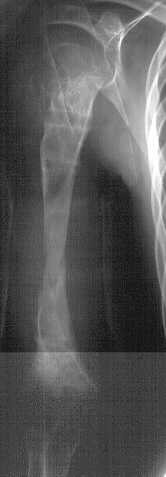

Radiological examination showed absence of proximal epiphysis of the right humerus with marked deformity of the metaphyseal region. There was mild shortening of the right tibia in association with destruction of the lateral part of the proximal metaphysis and epiphysis. The diagnosis was neonatal sepsis with multifocal osteomyelitis involving the right humerus and proximal right tibia.

Xrays at age 11 show significant angualtion developed in the humerus . However tibial growth was good .